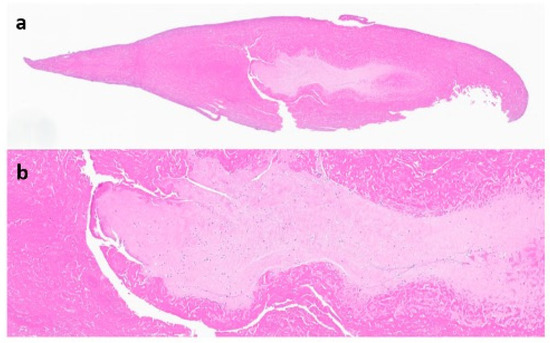

The suprapatellar pouch was found to be filled with a large number of smooth, white and loose rice bodies. The synovial fluid and rice bodies were collected for pathology and culture (Figure 4). The remaining loose bodies were excised from the knee using a grasper, arthroscopic shaver, and bipolar electrocautery. In addition to rice bodies, there were extensive synovitis and adhesions present, which were excised with a combination of an arthroscopic shaver and bipolar electrocautery. Given the patient’s need for anticoagulation due to a history of DVT and APS, care was taken to cauterize all possible bleeding sources within the knee. The implant interfaces were carefully examined, and they were all found to be well fixed. An arthroscopic synovectomy was performed, leaving the implants in place. A pathological examination revealed chondroid metaplasia covered by fibrin-like material (Figure 5). Upon careful histopathological examination by our pathologist, the structures that were originally identified as rice bodies were in fact small loose bodies from SC. This unusual case represents a rare instance where SC was initially mistaken for the more commonly seen rice bodies found in RA.

Figure 5. Microscopic display of a loose body after paraffin-embedded sectioning (a), hematoxylin and eosin (HE) stain, 20× magnification (b).